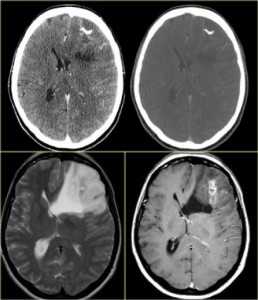

КТ и МРТ головного мозга. Аксиальные КТ, Т2-взвешенные МРТ и МРТ головного мозга с контрастировавшем. Вовлечение коры при олигодендроглиоме.